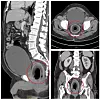

CT-bildene viser hvordan kokosnøtten hadde plassert seg inn i bukhulen på mannen. Foto: Reuters

CT-bildene viser hvordan kokosnøtten hadde plassert seg inn i bukhulen på mannen.

CT-bilder av mannen viser kokosnøtten sittende fast i pasientens endetarmshule, presset mot urinrøret i prostata og fikk blæren til å hovne opp. Legene prøvde først å få mannen til å presse ut kokosnøtten gjennom anus, men siden den var for stor, måtte de operere den ut.

Kokosnøtten målte rundt 7,5 centimeter lang og 5,7 centimeter bred ved bunnen. De tappet også rundt to liter urin som mannen hadde samlet i to dager.